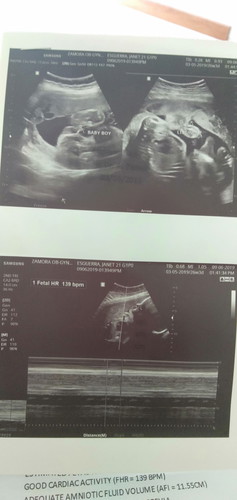

Hi ask Kulang Kung sino naka experience Dito ng nilalabasan everymorning ng kulay brown minsan parang light pink Sa pwerta nag pa ultrasound naman Ako and laboratory Sabi Ng ob KO WALA naman DAW problema Pero binigyan Niya Ako Ng 10 dupbaston isang beses isang araw pinapainom sakin 6months Napo tyan KO ?

Mummy of 1 superhero little heart throb